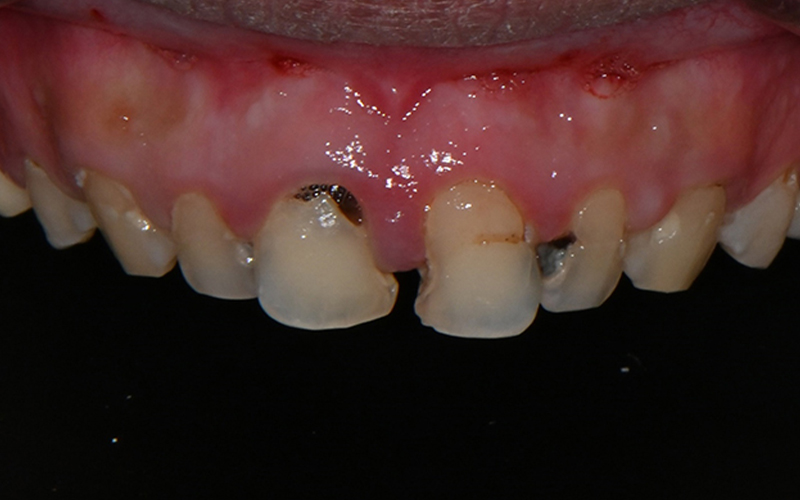

💛 First Visit 💛

The patient we are introducing had several cavities in progress,

and the pain would come and go,

which made it even easier to miss the right timing for treatment.

Looking at the before-treatment photos,

the front teeth had large cavities and damage

to the point that it was hard to smile,

and the areas filled with resin here and there

were also a major source of aesthetic stress.